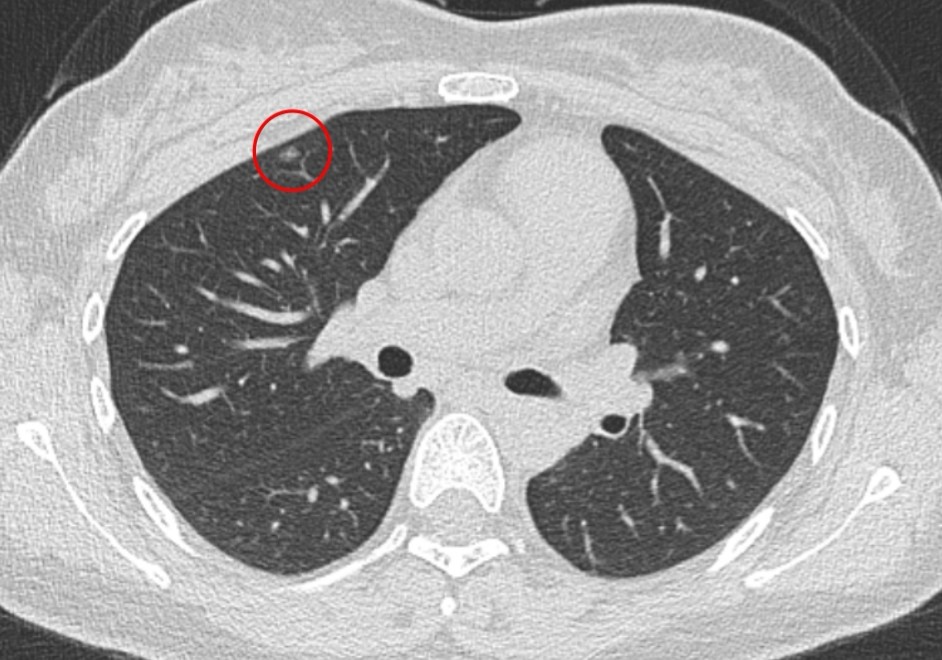

患者為年輕女性,14 年前曾因左下肺支擴(kuò)伴不張接受左下肺葉切除術(shù),2 年前復(fù)查時(shí)發(fā)現(xiàn)左前縱隔占位及右上肺磨玻璃結(jié)節(jié)。隨訪(fǎng)兩者均增大,考慮胸腺腫瘤及右上肺早癌可能,需盡快手術(shù)治療。但由于患者縱隔腫物位于左前縱隔,且合并右上肺病灶,若采用傳統(tǒng)側(cè)胸入路,難以同時(shí)完成兩處病灶切除,手術(shù)難度極大。

陳新富主任團(tuán)隊(duì)對(duì)患者病情進(jìn)行充分細(xì)致的術(shù)前討論,綜合評(píng)估病灶位置、既往手術(shù)史及身體狀況后,決定采用劍突下入路為患者實(shí)施“全胸腺切除 + 右上肺結(jié)節(jié)切除”術(shù),手術(shù)過(guò)程流暢順利。患者術(shù)后第二天即拔除胸管,下床活動(dòng)。